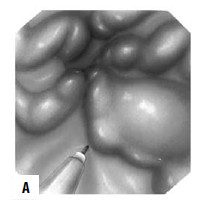

Рис. 85. Эндоскопическое лигирование варикозных вен пищевода

Для каждого вида кровотечения применяют свой метод гемостаза. Важно выбрать адекватный способ, поскольку второй попытки остановки кровотечения может и не представиться. Для определения источника кровотечения используют срочную фиброэзофаго‑гастродуоденоскопию (ФЭГДС), во время которой подтверждают диагноз варикозного расширения вен пищевода, определяют зону нарушения целостности вены и интенсивность кровотечения. При умеренном кровотечении из варикозных вен пищевода, синдроме Мэллори‑Вейса или язвы двенадцатиперстной кишки сразу может быть предпринята попытка его эндоскопической остановки. Наиболее эффективным методом остановки кровотечения из варикозных вен пищевода является их эндоскопическое лигирование. При этом эффективность метода достигает 90 %, а количество рецидивов составляет примерно 10 % (рис. 85).

Рис. 86. Зонд Блэйкмора. А – общий вид; Б – схема постановки

При интенсивном кровотечении, когда невозможно найти участок с нарушенной стенкой вены, при тяжелом состоянии больного показана постановка зонда Блэйкмора (с его установки и следует начинать лечение в большинстве случаев, так как эндоскопический гемостаз пока возможен не во всех учреждениях, да и в ночное время может не быть нужного специалиста и соответствующего технического обеспечения, а, кроме того, эндоскопический гемостаз на высоте кровотечения может быть технически невыполним, так как кровь будет заливать оптику). Эффективность метода достигает 85 %, а количество рецидивов – 50 % (рис. 86). Баллонная тампонада зоны кровотечения позволяет временно его остановить, после этого проводится гемостатическая терапия и восполняется кровопотеря. Через сутки давление в баллонах снижают. При остановке кровотечения могут быть предприняты попытки эндоскопической профилактики кровотечения путем паравазальной склеротерапии (при этом эффективность метода составляет около 90 %, а рецидивы кровотечения возникают почти в 30 % случаев) или эндоскопического лигирования вен пищевода (рис. 85; рис. 87).